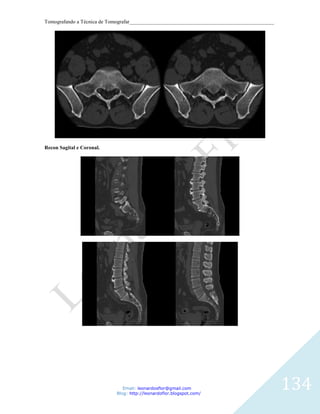

RECONSTRUCOES CORONAL E SAGITAL.

Email: leonardosflor@gmail.com

Blog: http://leonardoflor.blogspot.com/

65

Tomografando a Técnica de Tomografar_______________________________________________________

66